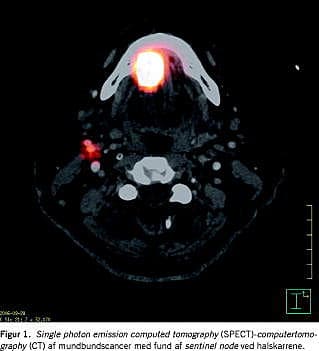

Den første lymfeknude, som modtager lymfedrænagen fra primærtumoren, benævnes sentinel node (SN), på dansk vogter- eller skildvagtknude, fjernelse af den er en ny kirurgisk behandlingsmetode. SN antages at være den lymfeknude, der har størst sandsynlighed for at modtage metastaser fra primærtumoren [3]. Enten dagen før operationen eller samme dag injiceres der radioaktivt mærkede partikler peritumoralt, hvorefter SN identificeres ved brug af lymfeskintigrafi, evt. med single photon emission computed tomography (SPECT)-computertomography (CT) (Figur 1 ), hvorved den præcise lokalisation fastsættes. De ved lymfoskintigrafien fundne SN identificeres under operationen ved brug af en håndholdt gammaprobe, hvorefter de eksstirperes og sendes til histologisk undersøgelse. SN undersøges efterfølgende minutiøst histologisk ved brug af tynde seriesnit og supplerende immunhistokemi, til identifikation af mikrometastaser foruden isolerede tumorceller. Teknikken er velkendt i behandlingen af modermærkekræft og brystkræft.

Behandlingen muliggør en målrettet behandling af halsens lymfeknuder og er med til at individualisere behandlingen, således at alene de patienter, som har lymfeknudemetastaser herunder mikrometastaser, får foretaget en efterfølgende fuld dissektion af halsens lymfeknuder.